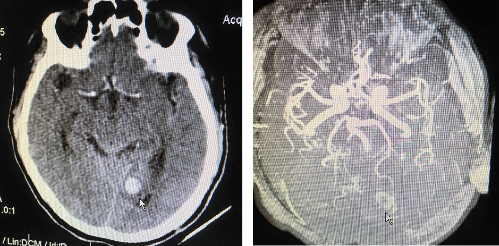

Nam bệnh nhân được đưa vào cấp cứu tại Bệnh viện Trưng Vương sau khi ngã khoảng 2 giờ. Kết quả chụp CT Scan cho thấy bệnh nhân xuất huyết dưới nhện hai bán cầu đại não và khối tăng đậm độ bằng máu nhu mô não vùng chẩm trái bờ đều nghi xuất huyết, u hoặc phình động mạch não. Chụp CT có tương phản, các bác sĩ phát hiện khối này tăng quang. Chụp MRI tương phản cho thấy rất nhiều tổn thương trên não.

Kết quả chụp kiểm tra của bệnh nhân.

Bác sĩ Trần Minh Thiệu, Khoa Chẩn đoán hình ảnh cho biết bệnh nhân được chẩn đoán nhồi máu não cấp, xuất huyết não trên nền dị dạng mạch máu não. Đặc biệt tình trạng xuất huyết dưới nhện hai bán cầu khả năng do AVM mạch máu não chẩm trái nuôi bởi động mạch não sau trái dẫn lưu tĩnh mạch màng não. Theo bác sĩ Thiệu, điều này đã xuất hiện từ lâu nhưng bệnh nhân không biết, lâu dần dẫn đến vỡ gây xuất huyết nguy hiểm.